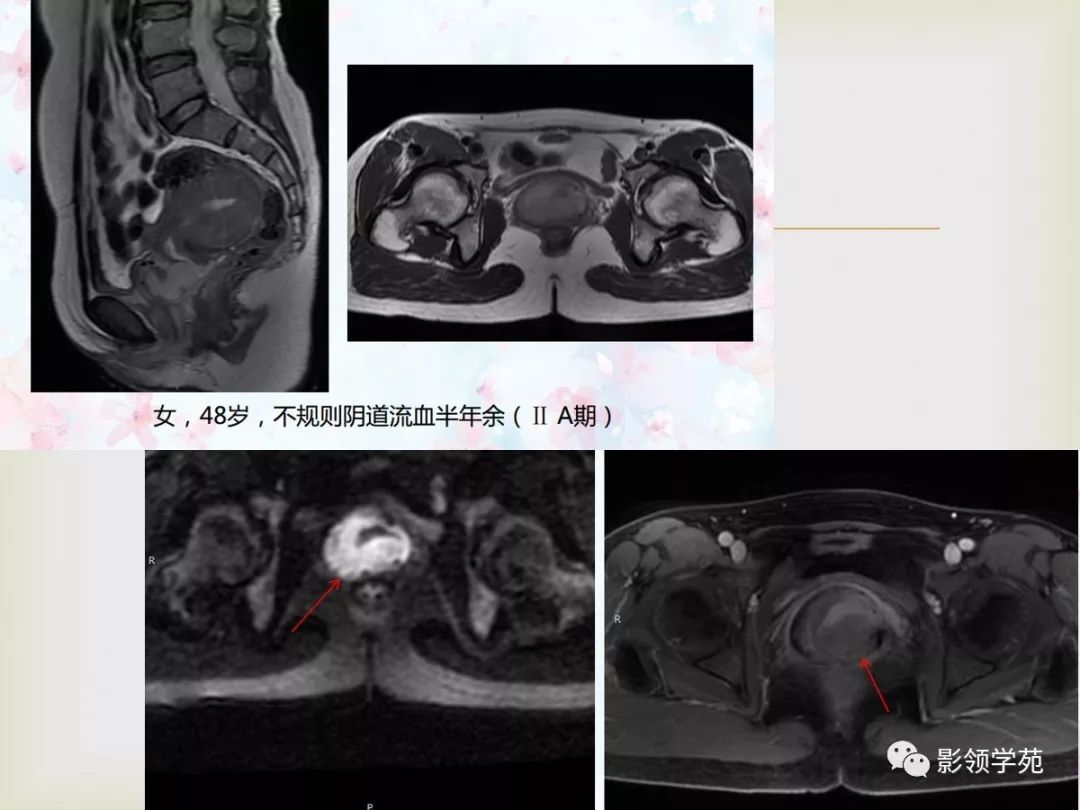

子宫憩室核磁共振图片,子宫憩室图片

子宫的磁共振图像

子宫卵巢病变的mri诊断

图 1,子宫肌瘤核磁共振图像

核磁共振平扫加增强,子宫腺肌症